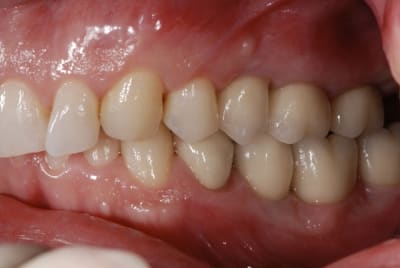

Le support paro est stable depuis 3 ans et la maintenance parfaite. je pense ici qu'un traitement ortho serait une bonne solution. j'ai déjà effectué un traitement similaire sur une 12 égressé ( confère photo ci-joint) et même si comme certain l'ont décrit, on a quelques aléas a cette méthode, ca vaut le coup d'essayer.

Merci dancha d'intervenir, j'avoue que j’espérerai bien que ce cas te face sortir de ta tanière et tes conseils sur eugenol m'avaient bien aidé pour réaliser le traitement ci-dessous.

Elle est en pleine forme cette 11, pas de mobilité un bel os, je vais essayer de la garder, sinon si ça marche pas, ben on l’enlèvera, en attendant je vais lui laisser sa chance.